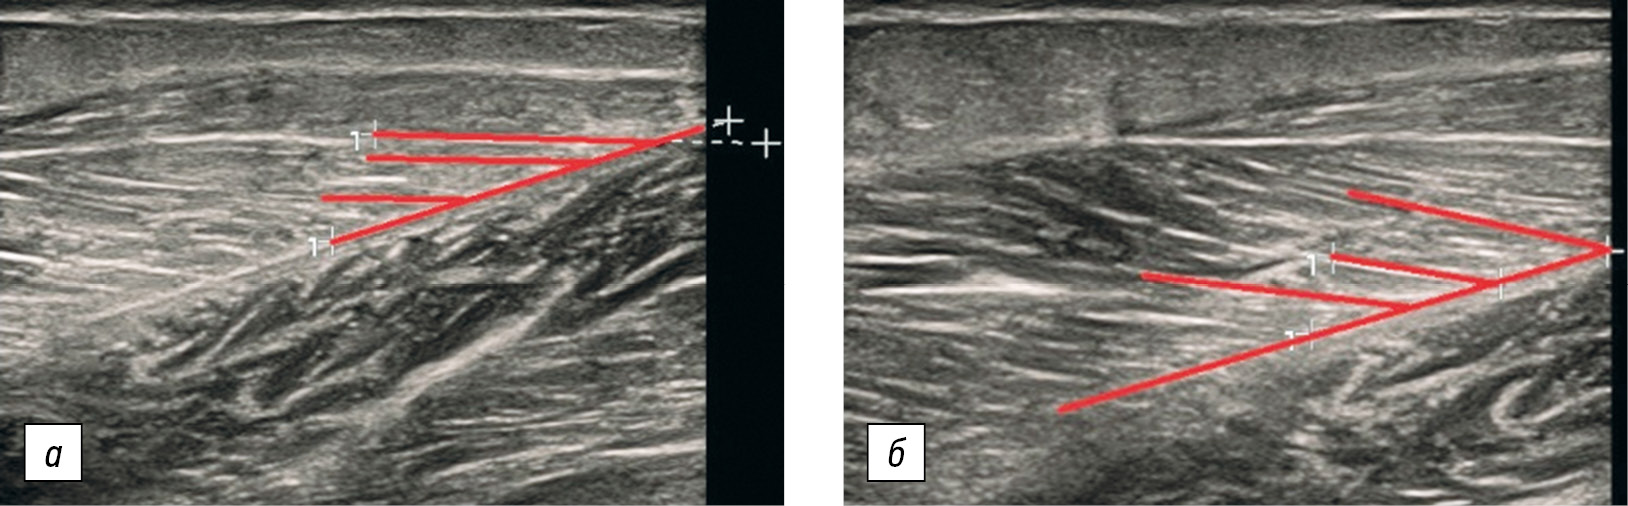

Как следует из в табл. 2 и 3, УП медиальной головки икроножной мышцы и камбаловидной мышцы продемонстрировал достоверное увеличение, тогда как для латеральной головки икроножной мышцы данный показатель статистически значимо не изменился. На рисунке представлены ультрасонограммы медиальной головки икроножной мышцы пациента с ГПУАС до начала программы стретчинга и через 6 мес. ее регулярного применения.

Рисунок. Ультрасонограммы медиальной головки икроножной мышцы пациента с гипермобильным плоскостопием и укорочением ахиллова сухожилия — увеличение угла пеннации: а — до начала программы стретчинга; б — через 6 мес. ее регулярного применения